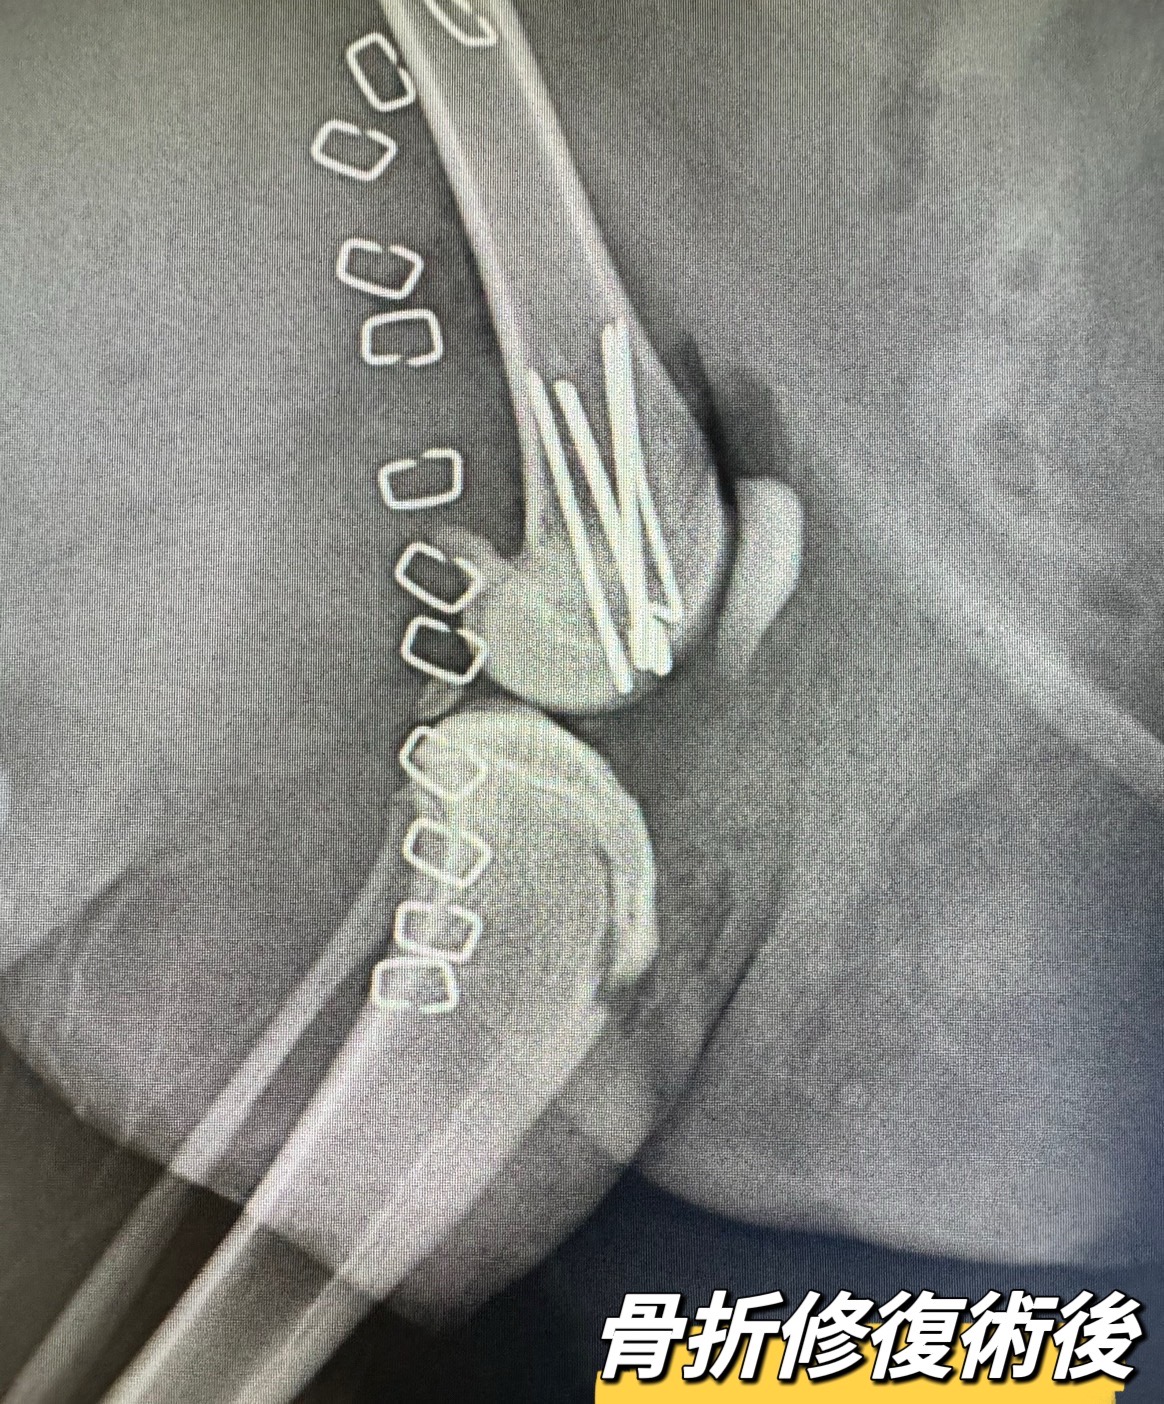

股骨遠端生長板骨折

#股骨遠端生長板骨折

所幸經過手術復位固定後,骨頭很快的癒合‼️

【股骨遠端生長板骨折】

幼年動物特有的骨折方式

主要發生在生長板尚未關閉的年輕動物

一般透過骨釘即可提供穩定固定

幼年動物骨頭癒合快速

需把握黃金期,盡早治療